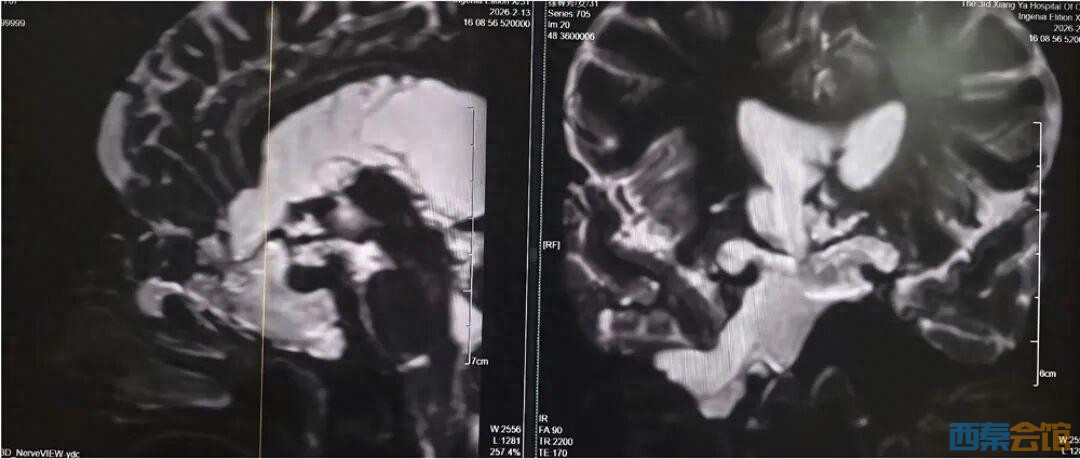

4年前,刘女士开始出现鼻腔流血、反复清水样流液,并伴有嗅觉减退。期间,她曾辗转多家医院及诊所就诊,医护人员多以“炎症”为病症进行对症治疗,但症状始终未得到根本改善。此后,刘女士多次出现发热伴鼻腔流液的情况,却一直未能明确病因,病情反复迁延。2026年2月11日,刘女士病情突然恶化,突发高热,体温超过39℃,并出现神志模糊的症状。当地医院紧急诊断后,确诊其为“脑脊液鼻漏合并颅内感染”,并下达了病危通知。危急时刻,家属紧急将刘女士转送至湘雅三医院功能神经外科求治,寻求进一步救治。 刘女士入院后,湘雅三医院功能神经外科杨靓副主任医师团队第一时间为其完善影像及实验室检查。经系统评估与综合分析,专家团队明确诊断刘女士所患疾病为——与脑室相通的高流量脑脊液漏,且其颅内感染情况较为严重。

团队指出,此类高流量脑脊液漏病情复杂,治疗难度极高:若直接进行修补手术,术后极易因颅内压力过高导致修补失败;同时,若在感染未充分控制前贸然封堵漏口,可能因失去引流通道导致颅内压骤升,进而造成病情急剧恶化,甚至危及患者生命。 为确保治疗安全有效,经多学科讨论后,杨靓主任团队为刘女士量身制定了“先引流控制感染,后精准修补漏口”的阶梯式治疗方案,分阶段推进救治工作,最大限度降低治疗风险。